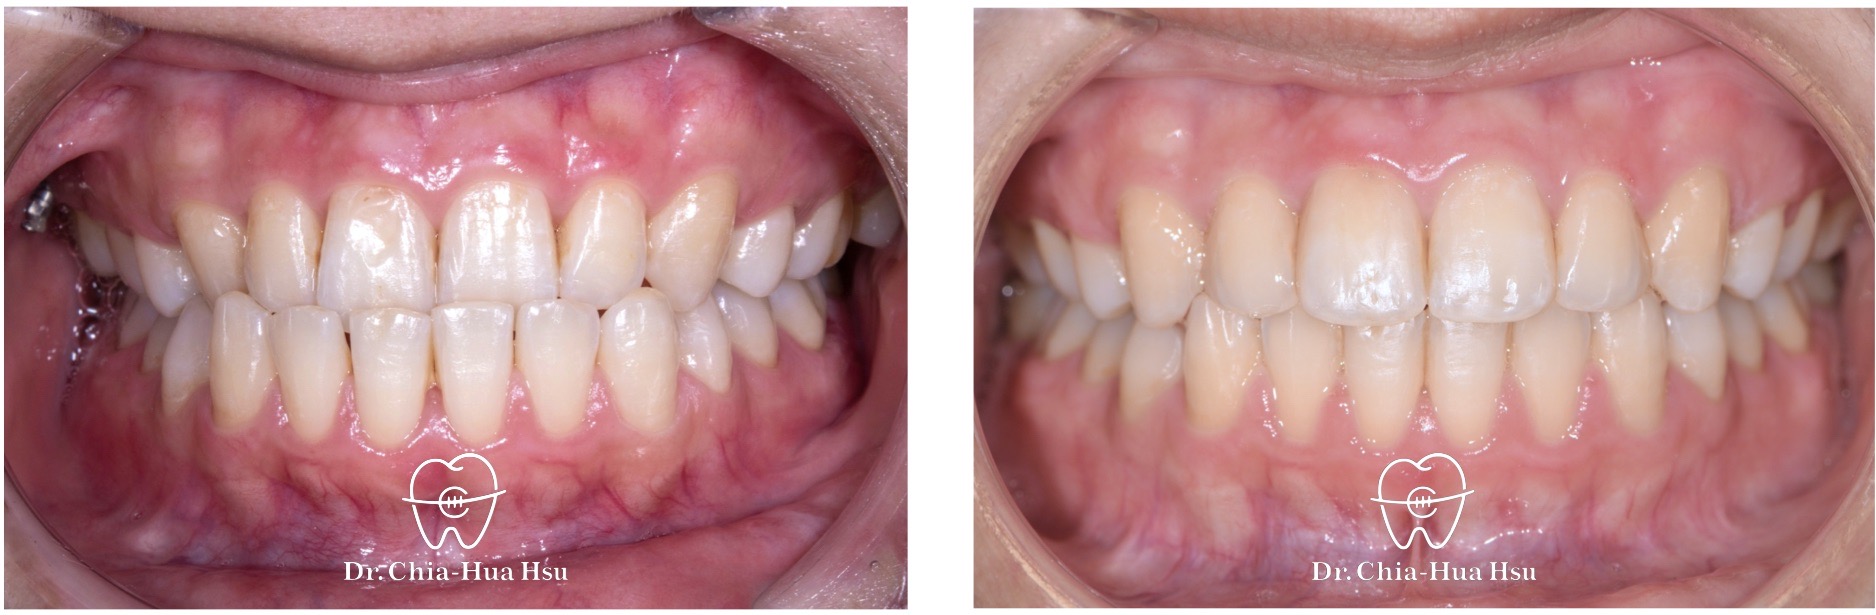

治療前

治療後